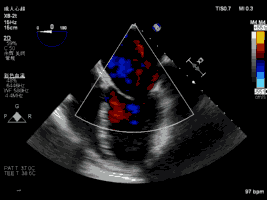

夹合术前:彩色多普勒示重度二尖瓣反流